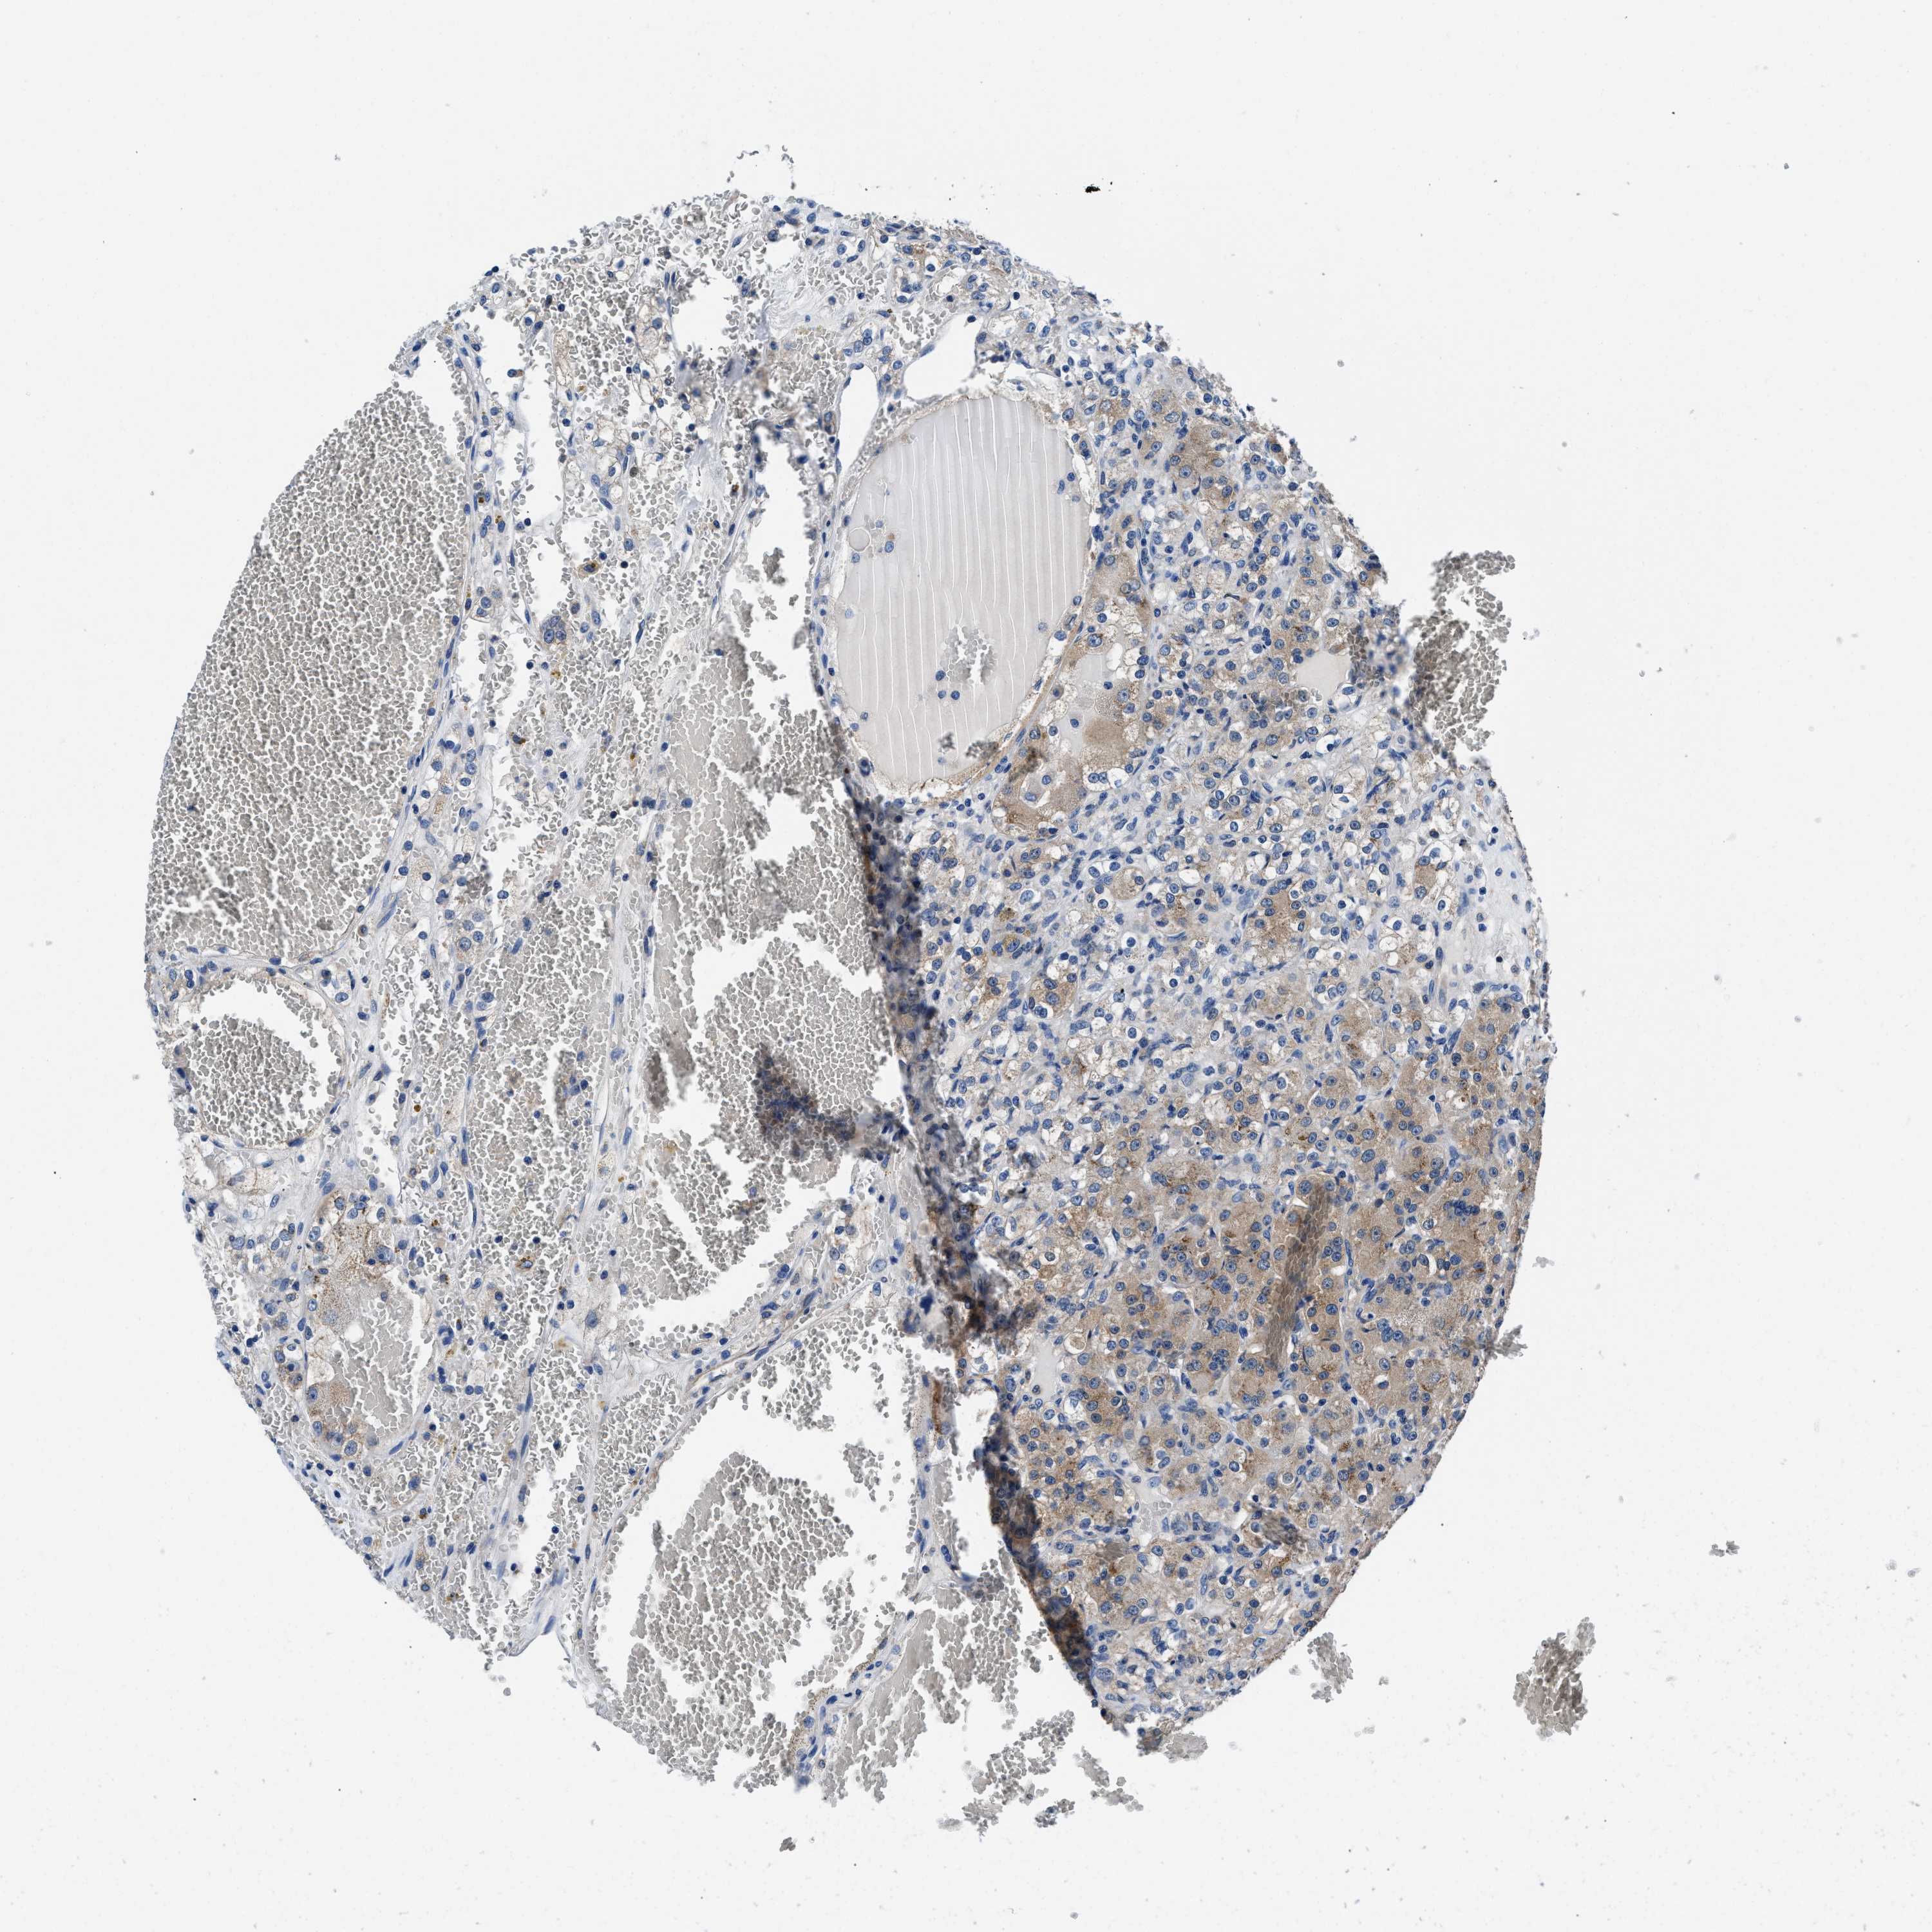

KIDNEY RENAL CLEAR CELL CARCINOMA (VALIDATION) - Interactive survival scatter ploti

The Survival Scatter plot shows the clinical status (i.e. dead or alive) for all individuals in the patient cohort, based on the same data that underlies the corresponding Kaplan-Meier plots. Patients that are alive at last time for follow-up are shown in blue and patients who have died during the study are shown in red.

The x-axis shows the expression levels (FPKM) of the investigated gene in the tumor tissue at the time of diagnosis. The y-axis shows the follow-up time after diagnosis (years). Both axes are complimented with kernel density curves demonstrating the data density over the axes. The top density plot shows the expression levels (FPKM) distribution among dead (red) and alive patients (blue). The right density plot shows the data density of the survived years of dead patients with high and low expression levels respectively, stratified using the cutoff indicated by the vertical dashed line through the Survival Scatter plot. This cutoff is automatically defined based on the FPKM cutoff that minimizes the p-score. The cutoff can be changed by dragging the vertical line or by entering a cutoff value in the square labeled "Current cut-off".

Under the Survival Scatter plot the p-score landscape (black curve; left axis) is shown together with dead median separation (red curve; right axis). Dead median separation is the difference in median mRNA expression between patients who have died with high and low expression, respectively. It is calculated as follows: median FPKM expression of dead patients with high expression - median FPKM expression of dead patients with low expression. This is intended to aid the user in visually exploring custom cutoffs and the associated p-scores and dead median separation.

Individual patient data is displayed and can be filtered by clicking on one or more of the category buttons on the top of the page. Categories describing expression level and patient information include: high, low, alive, dead, female, male and tumor stages. The scale of the x-axis can be toggled between linear and log-scale by clicking on the "x log" button. Mouse-over function shows TCGA ID, patient information and mRNA expression (FPKM) for each patient.

& Survival analysisi

Kaplan-Meier plots summarize results from analysis of correlation between mRNA expression level and patient survival. Patients were divided based on level of expression into one of the two groups "low" (under cut off) or "high" (over cut off). X-axis shows time for survival (years) and y-axis shows the probability of survival, where 1.0 corresponds to 100 percent.

NEU1 is not prognostic in Kidney Renal Clear Cell Carcinoma (validation)

Best expression cut offi

Based on the FPKM value of each gene, patients were classified into two groups and association between prognosis (survival) and gene expression (FPKM) was examined. The best expression cut-off refers the FPKM value that yields maximal difference with regard to survival between the two groups at the lowest log-rank P-value. Best expression cut-off was selected based on survival analysis .

When clicking on this number, the vertical dashed line indicating cut-off, the interactive survival plot, and the Kaplan-Meier curve will be adjusted to show results based on the best expression cut-off.

: 1.09

TCGA RNA samplesi

RNA-seq data is reported as average FPKM (number Fragments Per Kilobase of exon per Million reads), generated by the The Cancer Genome Atlas (TCGA) .

Normal distribution across the dataset is visualized with box plots, shown as median and 25th and 75th percentiles. Points are displayed as outliers if they are above or below 1.5 times the interquartile range. FPKM values of the individual samples are presented next to the box plot.

Average pTPM 1.4

Number of samples 100